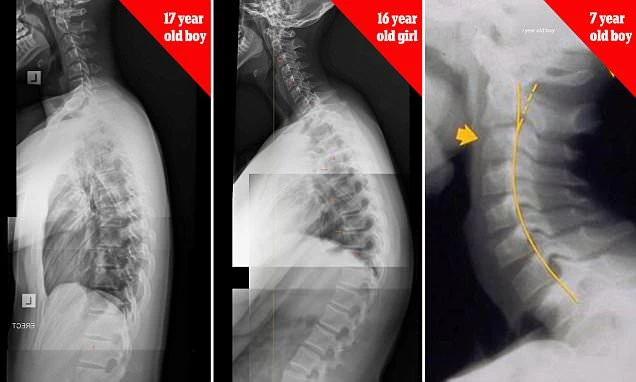

(Kiến Thức) - Những hình ảnh được chụp lại bởi bác sĩ người Úc, James Carter, cho thấy cột sống biến dạng nghiêm trọng vì nghiện smartphone.

Những hình ảnh chup X-quang cho thấy trẻ em từ 7 tuổi cho đến thanh thiếu niên có xương cổ và cột sống biến dạng nghiêm trọng do suốt ngày chúi mặt vào điện thoại thông minh.

Bác sĩ Carter cảnh báo rằng hiện tượng "text neck" (tạm dịch - cổ nhắn tin) - hậu quả của việc cúi xuống nhìn màn hình quá lâu do nghiện smartphone đang dần trở thành dịch bệnh trong giới trẻ.

Ông chia sẻ: "Đây là một hiện tượng đáng báo động. Theo quan sát của tôi trong những năm qua, số lượng bệnh nhân bị biến dạng cột sống tăng rất mạnh, trong đó 50% là thanh thiếu niên". Khi cột sống thoái hóa, những người này sẽ phải chịu những cơn đau đầu, cổ, vai và lưng.

Theo nghiên cứu của bác sĩ, những người sử dụng smartphone đang dành ít nhất 4 tiếng/ngày nhìn vào màn hình - tức là một năm họ mất đến 1.400 giờ, dẫn đến áp lực kinh khủng lên đốt sống cổ. Cụ thể, khi ta đứng thẳng, cổ sẽ phải chịu một áp lực khoảng 5kg. Tuy nhiên khi cúi xuống, tùy theo góc độ mà áp lực cổ phải chịu tăng dần, dao động trong khoảng 12,2 kg khi cúi 15 độ, đến 27 kg khi cúi 60 độ. Với áp lực khủng khiếp như vậy, lâu dần đốt sống cổ sẽ bị thoái hóa và biến dạng, tạo thành hiện tượng "cổ nhắn tin".

Đây là hình chụp X -quang xương sống của một thiếu niên 20 tuổi nghiện smartphone, tình trạng xương sống thoái hóa tương tự như một cụ ông 80 tuổi.

Hình X-ray cột sống của một cô gái 16 tuổi bị cong hình chữ S do hiệu ứng cúi xuống nhìn điện thoại.